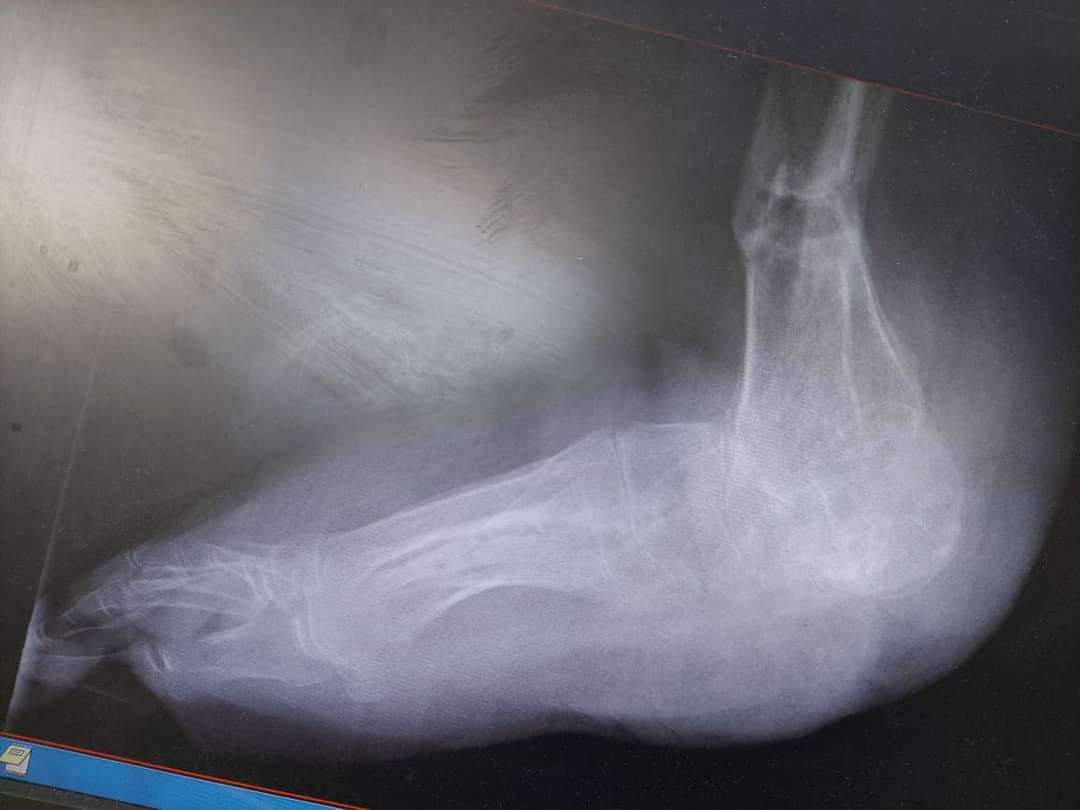

أجرى فريق طبي متخصص من دائرة العظام برئاسة أخصائي أول جراحة العظام المقدم الطبيب بسام الحراحشة عملية نوعية وهي الأولى من نوعها على مستوى المملكة تم فيها ترميم قدم فتاة تبلغ من العمر ١٩ عام بعد إصابتها بإلتهاب مستعصي في عظام القدم والكاحل بعد استنفاذ كل الطرق التقليدية في علاجها .

وقال المقدم الطبيب الحراحشة ان الفتاة راجعت عيادة العظام وعند التشخيص تبين وجود إلتهاب شديد في عظام الكعب والكاحل ،فتقرر بعد ذلك تحويل الفتاة إلى عيادة ترميم الأطراف لعلاجها بطريقه مبتكرة دون الحاجة إلى بتر القدم .

وبين المقدم الطبيب الحراحشة ان العملية اجريت على مرحلتين الأولى تم خلالها استئصال الأجزاء المصابة والمرحلة الثانية تم ترميم عظام القدم والكاحل عن طريق عظام الساق السليمة وتحويل جزء من عظام الساق لتحل مكان الجزء المستأصل من القدم مع إعادة تشكيلها بشكل ينسجم مع شكل القدم ويستطيع المشي عليها.